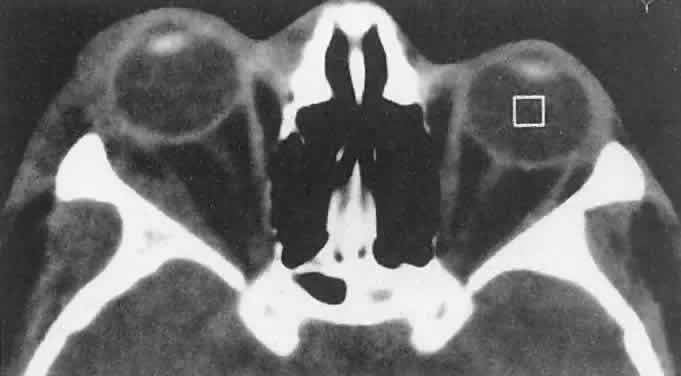

RHABDOMYOSARCOMA Rhabdomyosarcoma is the most common soft-tissue sarcoma in patients younger than 15 years of age and the most common primary orbital malignancy in childhood. These facts should not imply its frequent occurrence. Including all body sites, the annual incidence of childhood rhabdomyosarcoma in the United States is approximately 225 cases.2 The orbit is the site of origin in 5% to 25% of cases.3,4 However, site distribution varies with age. In children 5 to 9 years of age, for example, approximately 40% of primary rhabdomyosarcomas involve the orbit or eyelid.2 Although relatively rare, the tumor has a devastating natural history and demands a high index of suspicion in all cases of pediatric proptosis. Orbital rhabdomyosarcomas are slightly more common in females, with a 0.79 to 1 male-to-female ratio.2 The average age of presentation is 7.8 years, but the tumor may be present at birth and has been reported in patients as old as 78 years.5 A positive family history and associated anomalies have at times been identified, but these are exceptions rather than the rule. Classically, orbital rhabdomyosarcoma presents in an abrupt manner, with rapid progression of proptosis over days to weeks. A somewhat more indolent course does not exclude the diagnosis, however. Vigilance also should be exercised when rapidly expanding eyelid lesions are encountered. Rhabdomyosarcoma may present as ptosis or an eyelid mass rather than with proptosis.4 An eyelid rhabdomyosarcoma can occur as a congenital lesion.6 Within the orbit, rhabdomyosarcoma occurs most often, but not exclusively, in the superior nasal quadrant, with downward and outward displacement of the globe. CT scans show the topography of the orbital mass (Fig. 1A), as well as the possible extension into adjacent bone, paranasal sinuses, or the intracranial cavity. The circumscription that may be noted on CT is relative, because the lesion is not encapsulated and microscopically infiltrates normal tissue. Echography shows internal echoes of low-to-medium amplitude. Because the cellular tumor absorbs acoustic energy, the amplitude of the spikes falls off somewhat through the lesion (see Fig. 1B and C). MRI can help define the tumor's relationship to extraocular muscles (Fig. 2). The clinical diagnosis must be confirmed by biopsy. Because of the risk of seeding the biopsy tract, a transcranial approach should be avoided. If possible, the periosteum should not be violated because it presents a relative barrier to tumor invasion. Depending on its location, the lesion should be approached transconjunctivally or with an eyelid crease incision/transseptal dissection. The surgeon must balance the benefit of complete gross tumor resection with the risks of functional impairment and tumor dissemination that may accompany that effort. Tissue samples should be fixed in formaldehyde solution and glutaraldehyde for light and electron microscopic study. In addition, the value of immunohistochemical differentiation has been established for some time, and the potential uses of molecular genetic studies are rapidly emerging. Consequently, the procurement of fresh or frozen tissue, or both, has been given the highest priority by the Biopathology Discipline within the Intergroup Rhabdomyosarcoma Study Group (IRSG).2 These techniques can facilitate the diagnosis of poorly differentiated tumors, and they may refine diagnostic and prognostic classifications, identify candidate genes, and contribute to potential gene therapies. Since the inception of IRSG-I in 1972, the multicenter collaboration has enrolled the overwhelming majority of patients diagnosed with rhabdomyosarcoma in the United States and has contributed significantly to enhanced patient survival. Patients with orbital tumors had a 96% versus 83% failure-free survival in IRSG-IV compared with those in the IRSG-III.2 As of the year 2000, with the IRSG-V study underway, the overall (all primary sites) 5-year survival of children and adolescents with nonmetastatic and metastatic tumors was approaching 80%. This progress reflects advances in diagnostic imaging and multimodal treatment, including chemotherapy (e.g., agents, combinations, timing), radiation therapy (e.g., doses, fractionation, timing), and surgery (e.g., diagnostic biopsy, local staging, salvage procedures). Therapeutic protocols have evolved over the past 30 years, but they also have not been uniform at any given point in time. Rather, they have been tailored to the patient's level of risk, as determined by multiple prognostic factors (Table 3). The concept of “risk-appropriate therapy”7 recognizes, for example, that a 6-year-old child with an embryonal rhabdomyosarcoma confined to the orbit might do well with a relatively simple chemotherapy protocol, avoiding the late adverse effects of high-dose radiation. Conversely, an 18-year-old patient with an alveolar rhabdomyosarcoma arising in the retroperitoneum, with metastases at presentation, needs aggressive, complex chemotherapy and radiation, and may still do poorly. Prognostic factors considered by the multidisciplinary team include the presence of gross or microscopic residual tumor, and this determination currently is being redefined with molecular techniques that may show residual disease even without microscopic evidence2; whether tumor is confined to the anatomic site of origin or invades surrounding tissues; tumor size, with 5 cm considered a breakpoint; regional lymph node involvement; and distant metastasis. Body site plays a role, and the orbit is relatively favored. The age of the patient at diagnosis is a strong independent predictor of outcome.7 The current pathologic classification for childhood rhabdomyosarcomas by prognosis2 is as follows: